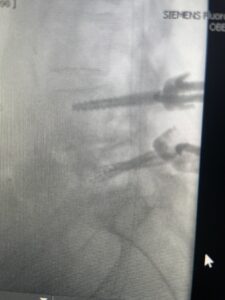

Fig 3: Lateral and AP fluoroscopic images demonstrating placement of pedicle screws for L4-5 fusion for spondylolisthesis.